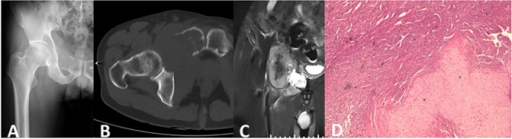

AP pelvis radiograph demonstrating a Grade 2 chondrosarcoma of the right proximal femur. There is an expansile lytic lesion with endosteal scalloping, cortical thickening, and characteristic rings and arcs (popcorn) calcification within the matrix. The lesion shows aggressive features with cortical destruction and soft tissue extension. MRI is required to assess marrow extent and soft tissue component.